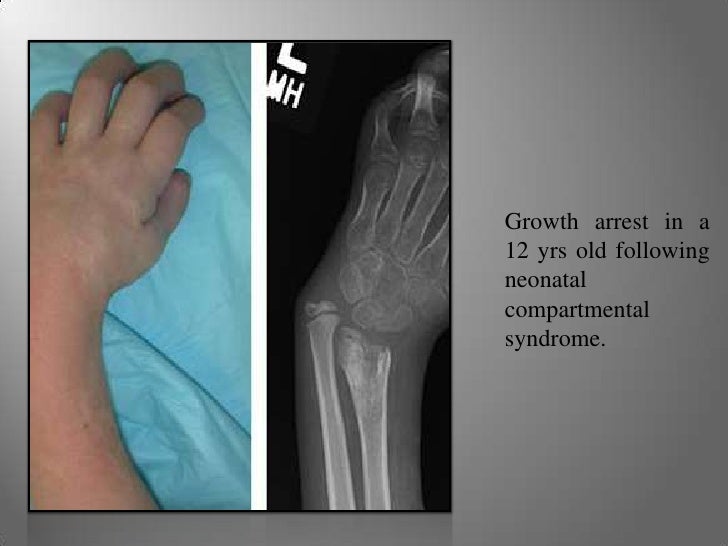

From www.slideshare.net